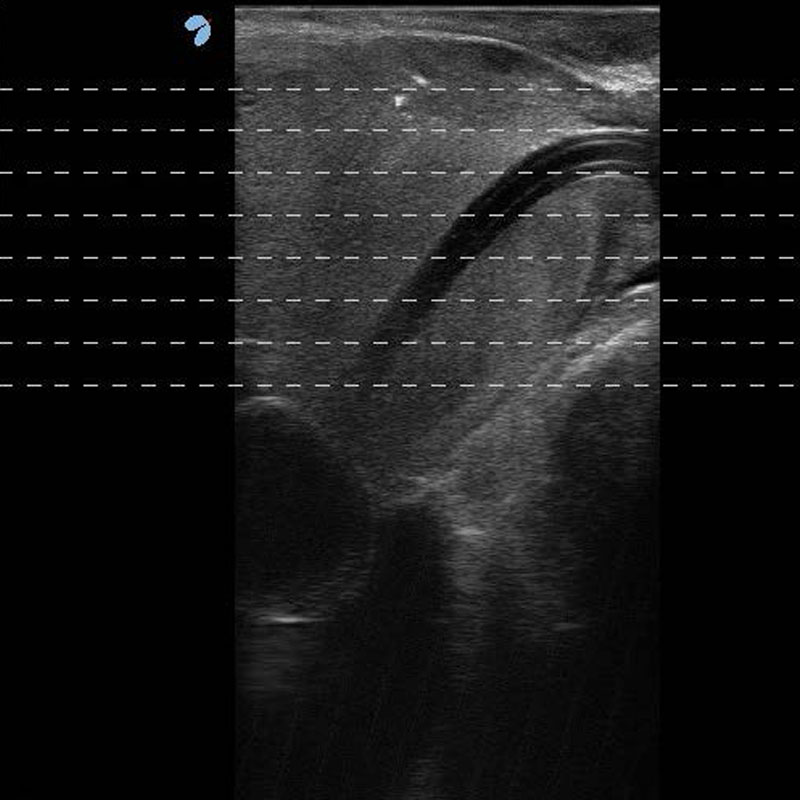

SoracteLite per il trattamento dell’IPB

Il trattamento SoracteLite consiste nell’inserimento per via percutanea di fibre ottiche (una o due fibre per lobo, in funzione del volume basale della ghiandola prostatica), tramite accesso transperineale (Transperineal Laser Ablation TPLATM), e nell’erogazione di energia laser per alcuni minuti che produce un riscaldamento del tessuto fino alla sua distruzione. Ciò causa una progressiva riduzione del volume del lobo prostatico (riduzione del volume almeno del 40% rispetto al volume basale ad 1 anno dal trattamento) e successiva scomparsa dei sintomi. La pianificazione del trattamento, l’inserimento degli aghi e il monitoraggio avvengono sotto guida ecografica.

Per facilitare la manovra di inserimento, il sistema dispone di un dedicato Sistema Guida multi-applicatore per sonda ecografica transrettale con il relativo Software di Pianificazione che visualizza le linee guida e l’area di ablazione stimata sullo schermo dell’ecografo.

In senso orario:

1. Sonda Esaote TRT33 con Sistema Guida multi-applicatore / 2. Software Biopsia

3./4. Sonda Esaote TRT33 dotata di Sistema Guida multi-applicatore